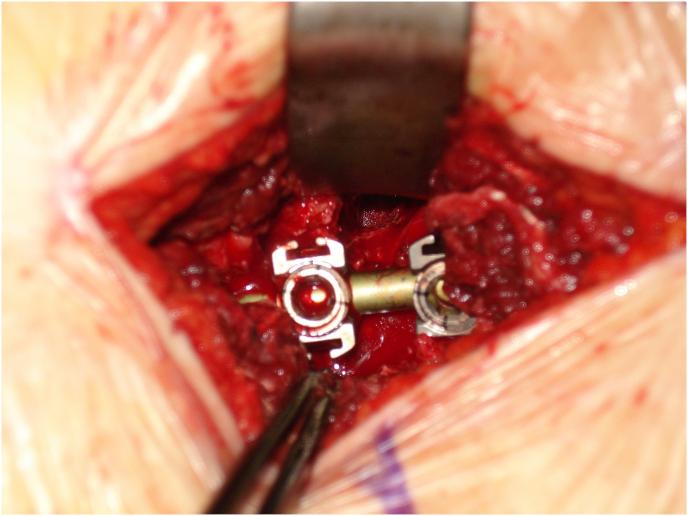

The technique facilitates bilateral canal enlargement through unilateral approach and provides accessibility to the contralateral foramen for decompression with perfect exposure and allows instrumentation through the lateral window with no muscle destruction.